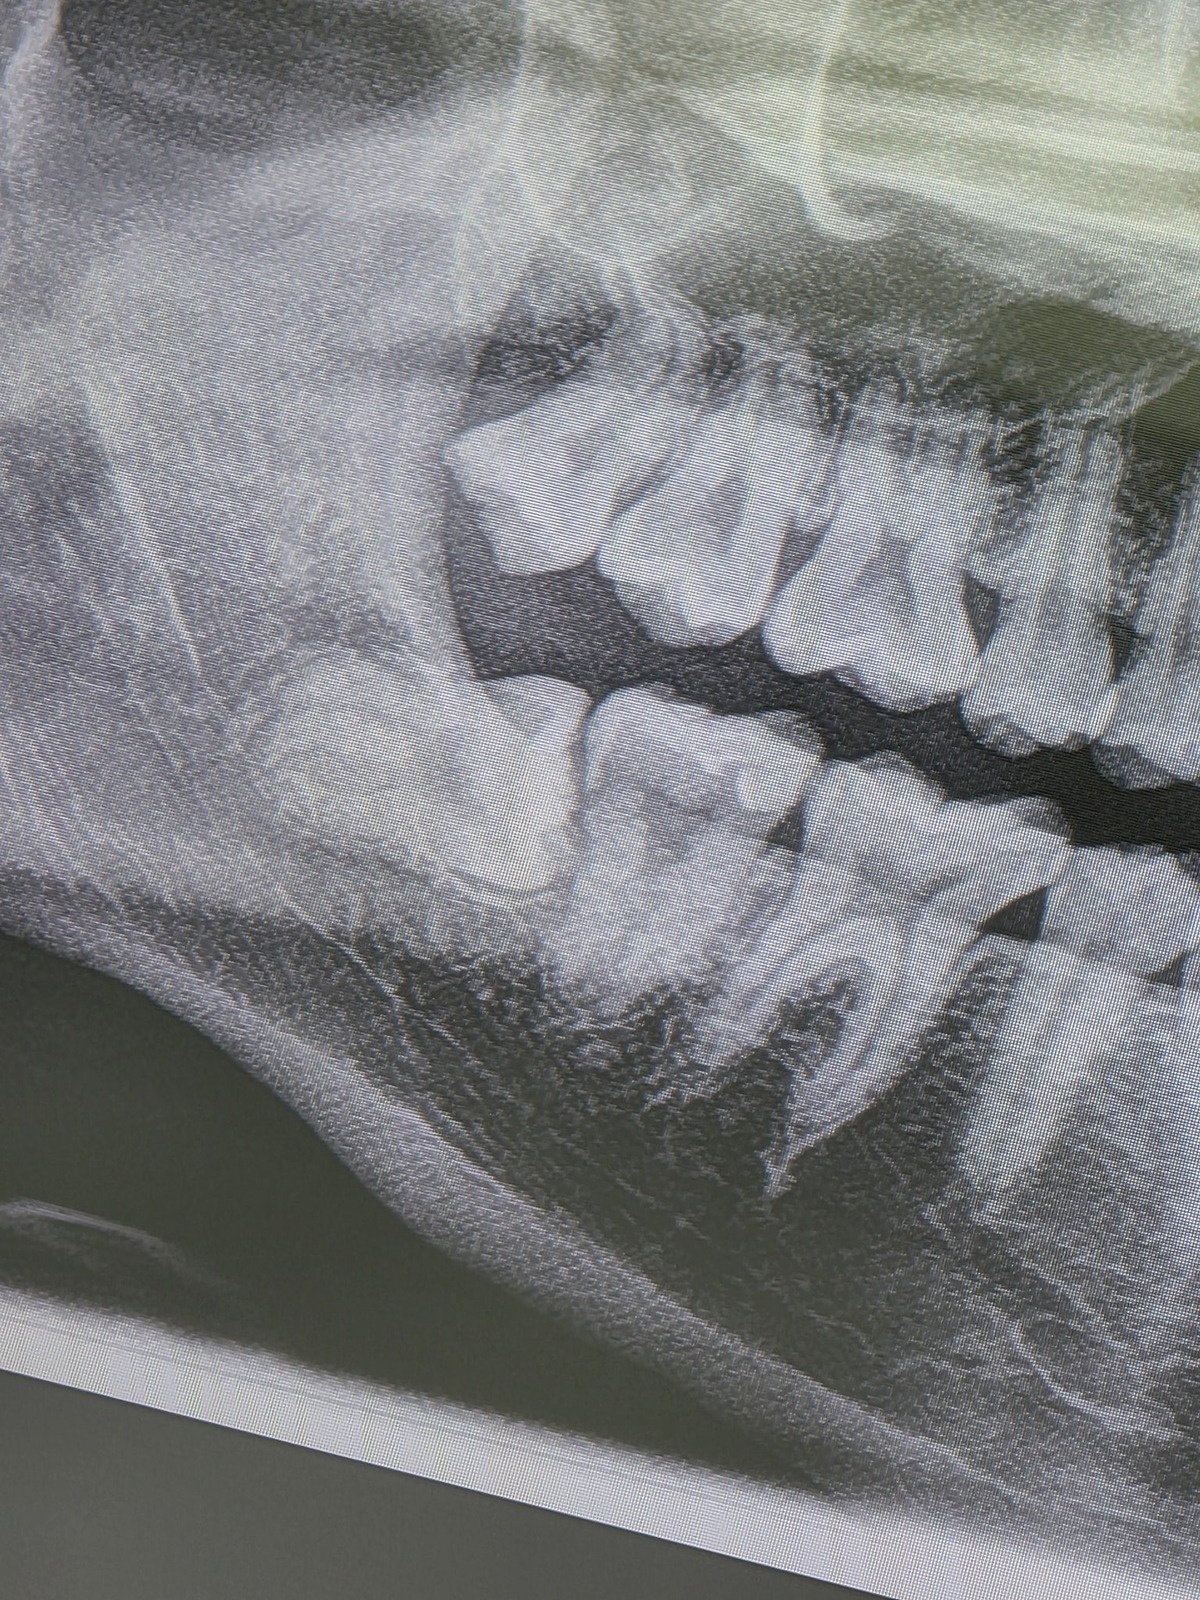

그리고 사랑니 뺀 스카이

사랑니 엑스레이 고맙다..